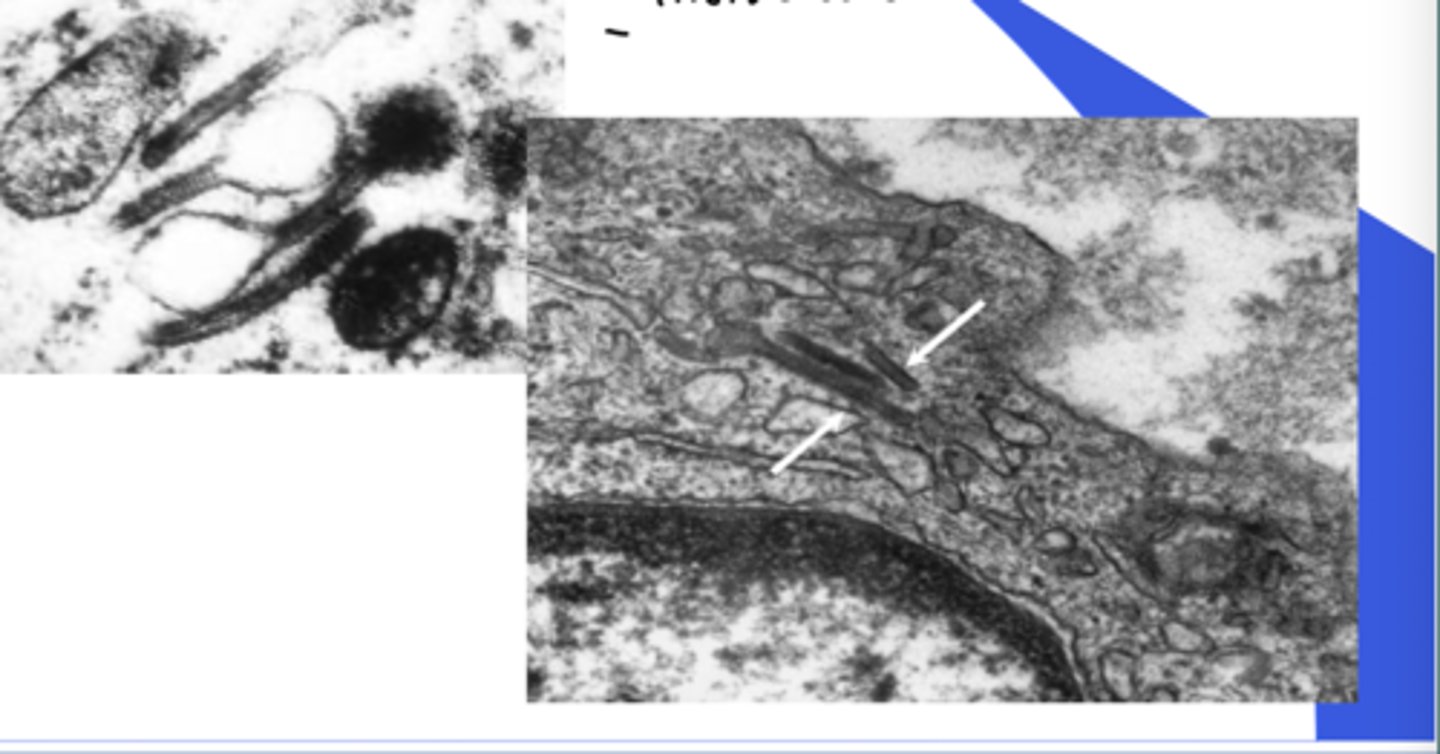

Langerhans cell disease - cells

Birbeck granules

- tennis racquet shaped cells